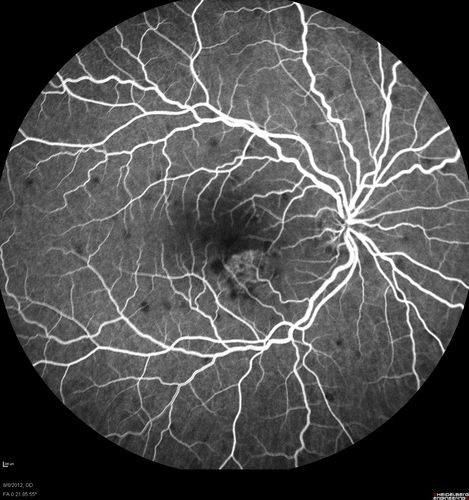

Punctate Inner Choroidopathy - PIC and Choroidal Neovascular Membrane - Right Eye - Fluorescein Angiogram

34-year-old woman with a change in vision in the right eye about eight days ago.  Her vision was hazy and she saw waviness in the vision.  She does have a history of aches and pains and she was diagnosed with Sjogren’s and 2 months ago she had some fevers and some sinus drainage and that went on for about two months.  She is a moderate myope.    OD 20/25, OS 20/20.